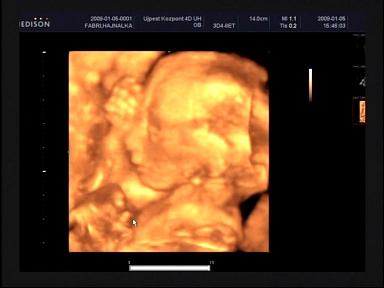

Ez a 4D ultrahang valójában egy számítógép által "kitalált" képet alkot, alapozva a 2D nyújtotta "vázlatokra", tehát nem túl pontos.

Meg a babáink még most kezdenek el iazán magukra szedni egy kis husit a bőr alá, úgyhogy az aszott múmia normális. :wink: :lol:

Nekünk például mondta a szonográfus, hogy úgy a 25-26. hét körül érdemes 4D-t csináltatni, akkor már van rajtuk egy kis "fognivaló" (ahogy felénk mondják), és az arca is mégjobban karakteresedik.